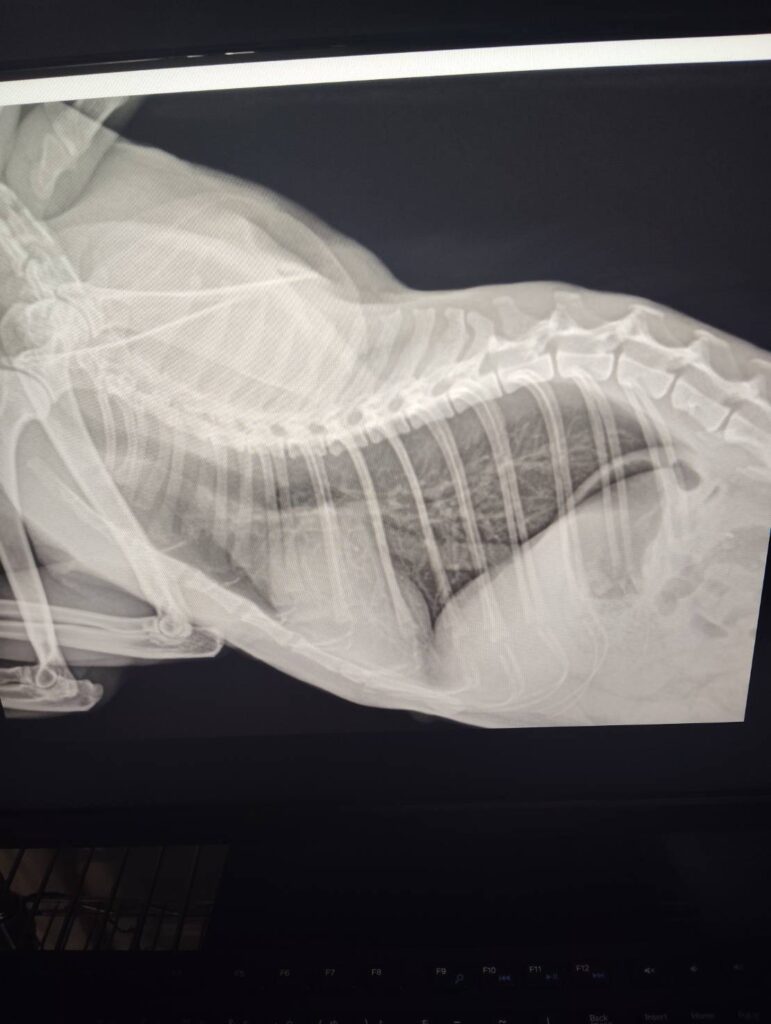

症例 猫 12歳 オス 来院理由 呼吸が早い、食欲がない 身体所見 呼吸回数96回 検査 【血液検査】 ・異常なし 【レントゲン検査】 ・心臓の輪郭不鮮明、心拡大 【心臓エコー検査】 ・左房拡大あり LAAO=1.8 ・心筋中隔壁 6mm 心筋自由壁8mm 診断 肥大型心筋症、肺水腫 方針 入院下で治療開始 3日後、状態良化のため、退院、内服開始し、定期検診の予定 実績に戻る 関連の症例を見る 循環器科 🫀犬の僧帽弁閉鎖不全症(心臓病)と肺水腫について